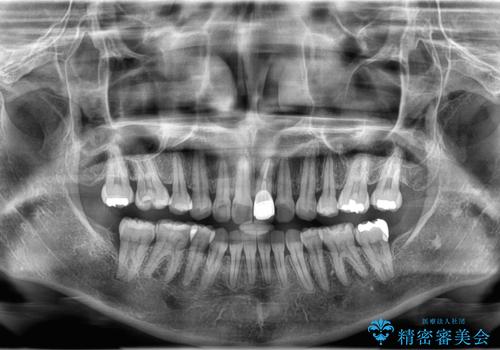

来院時、右下7遠心9mm、舌側6mmと深い歯周ポケットを認めました。

遠心から舌側、唇側に及ぶ深い垂直的骨欠損も認めたため、歯科衛生士による歯周基本治療の後、歯周外科(再生療法)を行いました。

レントゲン写真は、処置後一年経過時のもので、歯周ポケットは遠心4mm、舌側3mmまで減少、出血なし。

一度目の再生療法でできる骨形態は移行的でないこともあるため、経過を診つつ骨整形も必要であれば今後行う予定です。